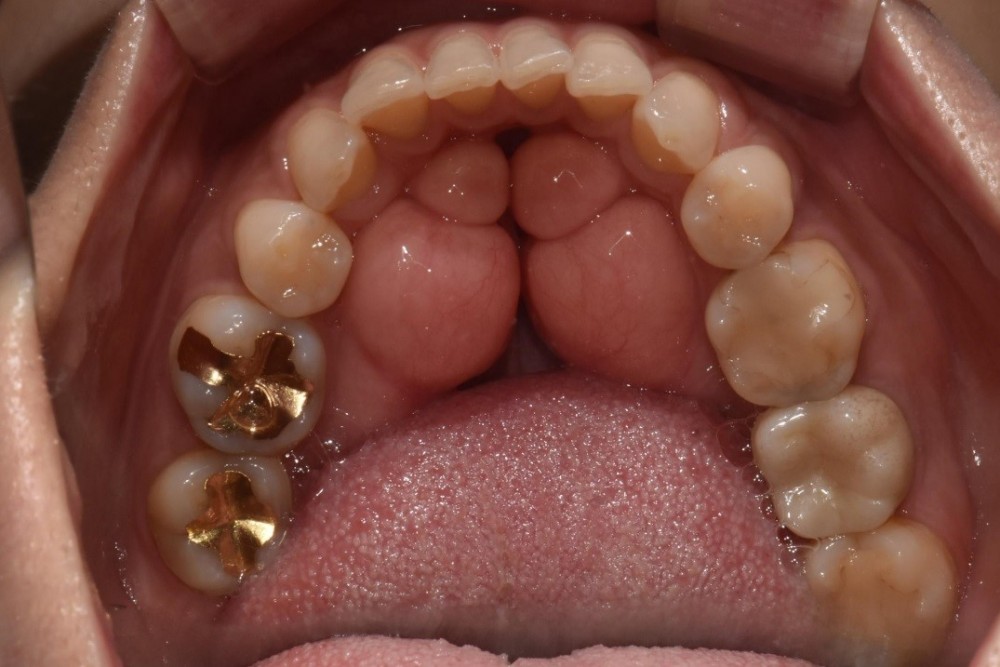

치료가 필요한 예시로 몇 달전에 성남에서 오신 여성 환자분입니다. (case.1)

![]()

입안에 가득한

골융기로 발음은 물론 저작력에도 문제가 나타납니다. 또한 입안에 상처가 빈번하게 생기게 되어 제거를

위해 저희 서울보스톤치과를 찾아주셨는데요. 몇 개의 대학병원에서 상담을 했지만 제거수술을 해주지 않았고

이곳 저곳 알아보다 상담을 받아보게 된 케이스입니다.

좌우측 골융기를 총 2회에 걸쳐 제거했는데 한 번에 모두 제거하기에는 환자에게 부담이 될 수 있기 때문에 이렇게 차례대로 제거하는 과정을 가지게 됩니다.